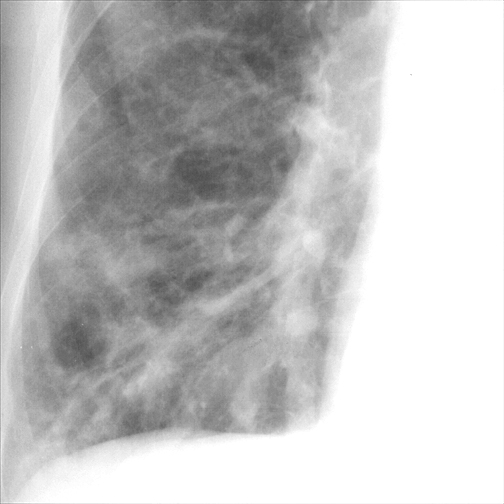

Bronchiectasis

Case 1 PA c/u